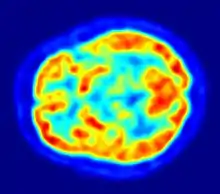

Apesar do rápido avanço científico, muito do funcionamento do cérebro continua um mistério. As operações individuais de neurônios e sinapses hoje são compreendidas com detalhamento considerável, mas o modo como eles cooperam em grupos de milhares ou milhões tem sido difícil de decifrar. Métodos de observação como registros de EEG e imageamento funcional cerebral mostram que as operações cerebrais são altamente organizadas, mas estes métodos não têm resolução suficiente para revelar a atividade de neurônios individualmente. Assim, mesmo os princípios mais fundamentais das redes de computação neural podem ficar, em grande medida, a serem descobertos por futuros pesquisadores.[5] O cérebro tem duas partes que ajudam no desenvolvimento: cerebelo e encéfalo.